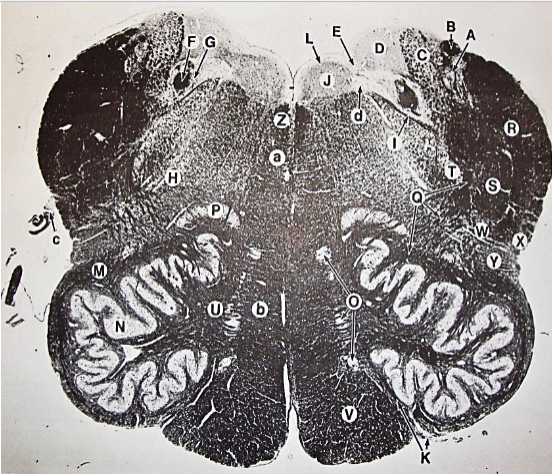

A

Lateral Cuneate nucleus

B

dorsal external arcuate fibers

C + D collectively

vestibular nuclei

C + D collectively

vestibular nuclei

E

dorsal motor nucleus of vagus nerve

F

solitary fasciculus

G

solitary nucleus

H

nucleus ambiguous

I

fascicles of glossopharyngeal nerve

J

hypoglossal nucleus

K

fascicles of hypoglossal nerve

L

dorsal longitudinal fasciculus

M

central tegmental tract

N

inferior olivary nucleus

R

inferior cerebellar peduncle

S

spinal trigeminal tract

T

spinal trigeminal nucleus

U

ventral trigeminothalamic tract

V

pyramidal (corticospinal) tract

W

rubrospinal tract

X

anterior spinocerebellar tract

Y

spinal lemniscus

Z

medial longitudinal fasciculus

a

tectospinal tract

b

medial lemniscus

c

vagus nerve

d

inferior salivatory nucleus

A + B collectively

vestibular nuclear complex

D

solitary fasciculus

E

solitary nucleus

F

nucleus ambiguous

G

fascicles of glossopharyngeal nerve

H

spinal trigeminal tract

I

spinal trigeminal nucleus

J

ventral trigeminothalamic tract

K

central tegmental tract

L

interior olivary nucleus

O

inferior cerebellar peduncle